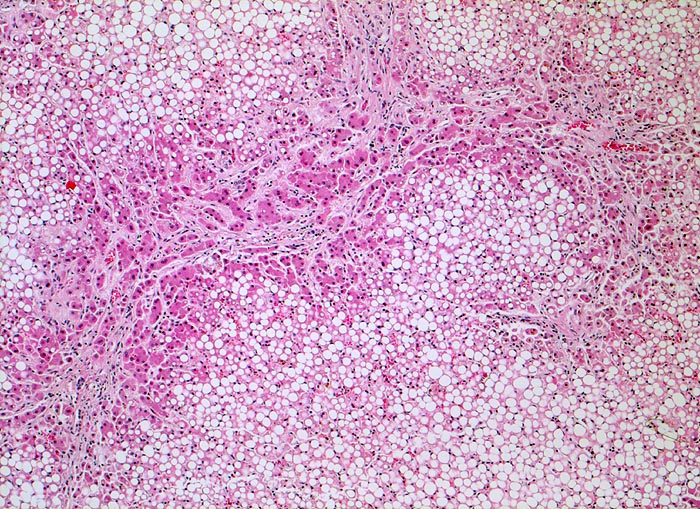

• Vollständiger feinknotiger zirrhotischer Umbau.

• Gemischtes portales, septales und intralobuläres Entzündungsinfiltrat.

• Floride sklerosierende alkoholische Steatohepatitis: Grobtropfige Verfettung von ca. 50% des Parenchyms.Neutrophile Granulozyten umgeben einzelne Hepatozyten (Satellitose). Wenig Apoptosekörperchen. Zahlreiche Mallory Körperchen und Megamitochondrien. Perivenuläre Maschendrahtfibrose.